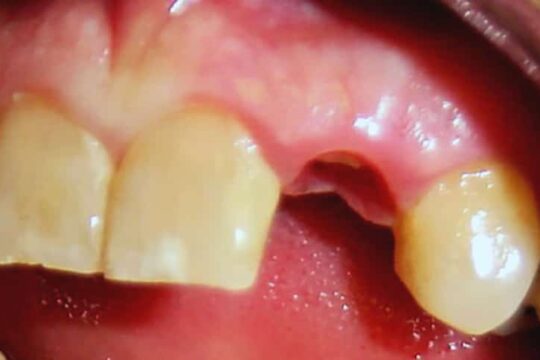

Impianto

Prima / Dopo